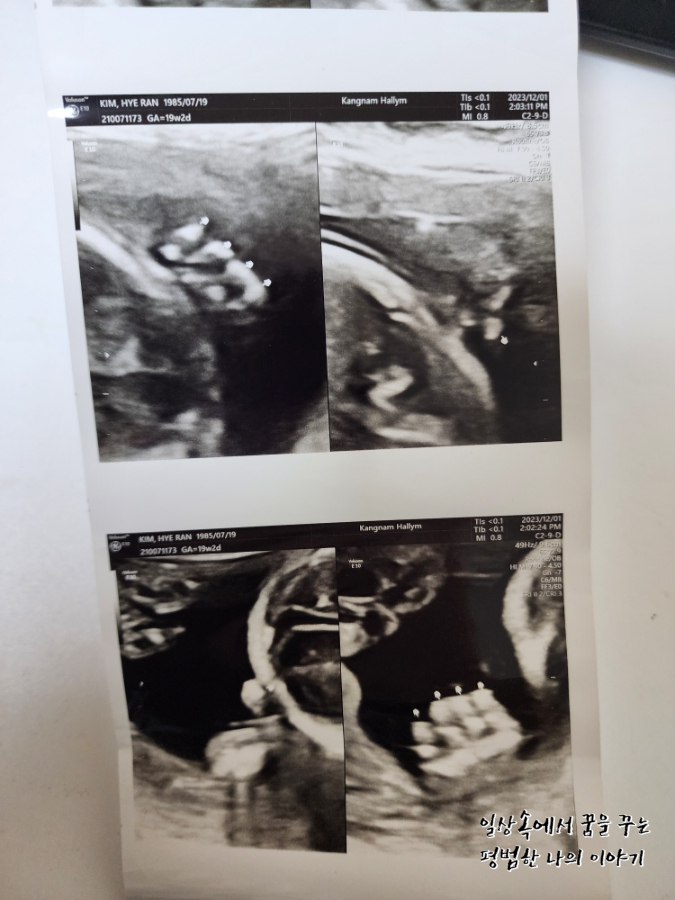

4주 만에 방문한 병원에서 삼등신이 된 아기를 만날 수 있었다. 이번에는 정확한 성별을 들을 수 있지 않을까 내심 기대했는데 아니나 다를까 정확하게 딸이라고 성별을 알려주셨다. 남편은 딸이라는 얘기를 듣자마자 이전부터 생각해뒀던 딸 이름으로 아기를 부르기 시작했다. 태동은 아직 느껴지지 않는데 이안이 때도 좀 늦게 느끼기 시작한 편이라 마음이 조급하지는 않다. 지금 걱정인 건 이안이 때는 임신 후반부터 아래쪽이 뻐근하고 아팠는데 둘째는 그 뻐근함이 너무 빨리 찾아와서 16주 정도 됐을 때부터 오후가 되면 붓기 시작해 서 있는 것조차 힘들어지기 시작했다. 의사 선생님께 괜찮은 거냐고 물어보니 다행히 아기한테는 아무런 영향이 없다고 하셨고 해결할 수 있는 방법은 역시나 출산뿐이라고 하셔서 버티는 수밖에 없겠구나 싶었다. 약간 자궁에 피고임이 있어 걱정이 되었는데 의사 선생님이 무리하지 말라고 하시더라. 자궁 내에 있는 피고임이라 증상이 악화돼도 알 수 있는 방법이 없기 때문에 배가 너무 아프거나 하면 바로 병원으로 오라고 하셨다.